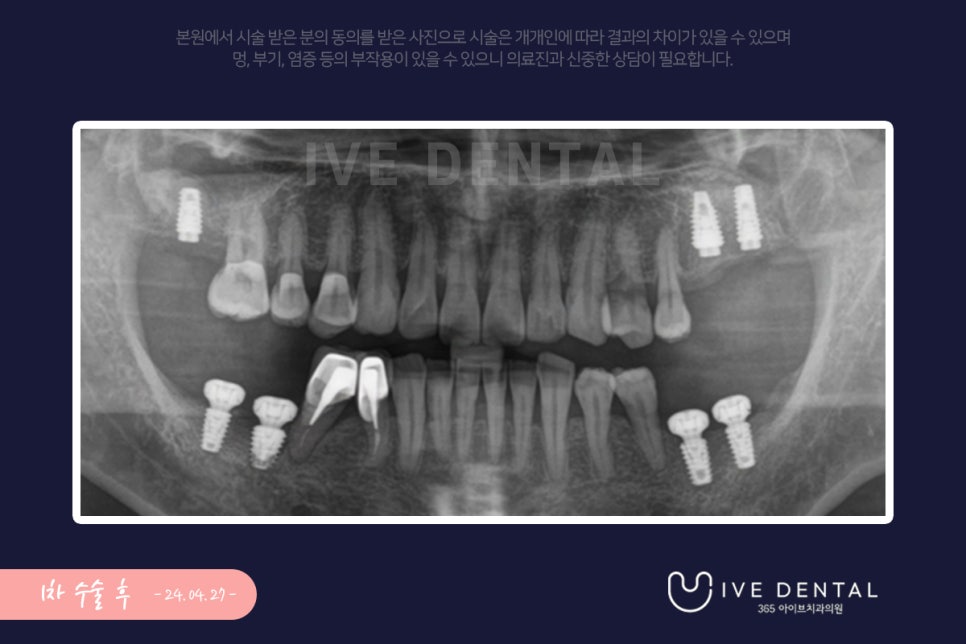

1차 수술 후의 사진입니다. 살릴 수 있는 치아는 최대한 살리고 염증이 너무 심하여 빠지기 직전의

치아는 발치 후 임플란트 시술을 진행하였습니다.

환자분의 잇몸 상태가 너무 좋지 않아 상악동거상술, 뼈이식 등 추가 수술을 같이 시행하였고요.

임플란트가 자리잡는 데 시간이 오래 걸릴 것으로 상되었는데요.

전주 임플란트 1차 수술 후 6개월 뒤 보철물을 올리는 것으로 계획을 잡았습니다.